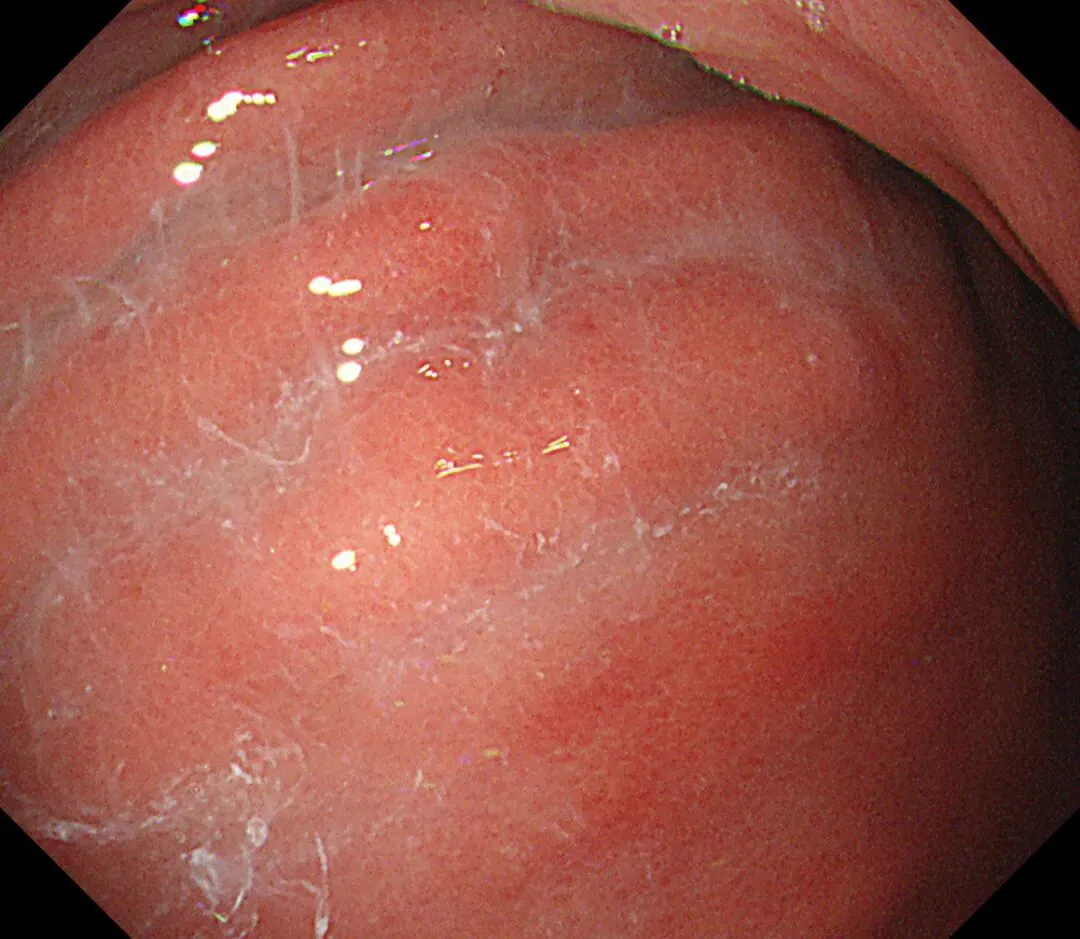

蛛网状黏液(web-like mucus):以胃底、胃体大弯为中心,有时可见白色透明、水洗难以去除的黏液附着,因外观与蜘蛛网相似而命名,多见于口服钾离子竞争性酸阻滞剂(P-CAB)患者,可能是因为其强效、持续抑酸作用所致,具体机制尚需进一步研究明确。

蛛网状黏液case1,服用P-CAB药物(具体服用时长不详)👇